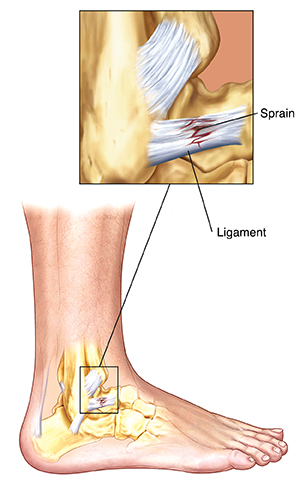

What is a sprain?

A sprain is an injury to a ligament (tissue that connects bones to other bones). Joints contain many ligaments. A sprain results when a joint is twisted or pulled and the ligament stretches or tears. Symptoms of a sprain are pain, swelling, and having a problem moving or using the injured area. Ankles, knees, and wrists are the joints most commonly sprained.

|

| A sprain is damage to a ligament. |